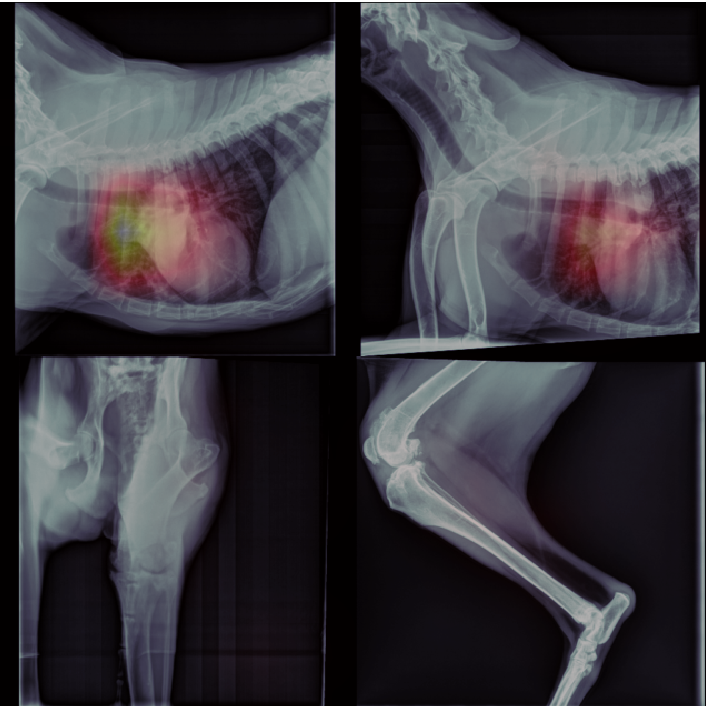

This section presents visualizations of the Vision Transformer (ViT) attention maps. The ViT used is specific to lung diseases, and the attention maps are shown for patients with the positive label ’Pulmonary Mass’. The input to the ViT is a concatenated feature map, and the X-ray images have been mapped and displayed with the same concatenation and transformations applied to the augmented feature maps.

The attention maps show that the ViT focuses on the thorax region where the lungs are located, as expected. The results also demonstrate that the ViT remains focused on the thorax area even with different contexts in the X-ray images. This highlights the robustness of ViTs.

The visualisation of the Vision Transformer (ViT) attention maps supports the conclusion that the attention is focused on the correct regions in the images and highlights the robustness of the network. This finding is particularly relevant for medical imaging, where the focus on specific regions of the images can be critical for accurate diagnosis.